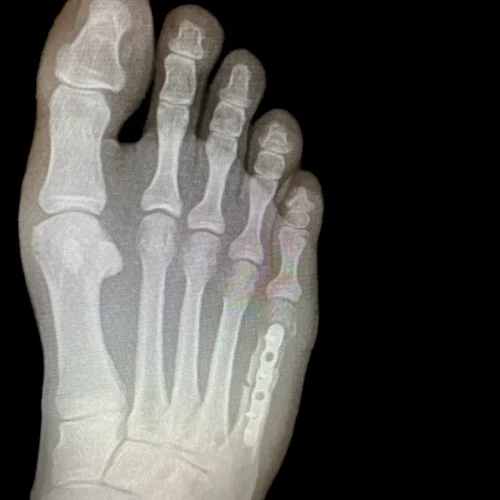

Surgical Intervention at Stepwell Institute is never a “one-size-fits-all” solution. We view surgery as a precise tool used to restore the natural biomechanics of the foot and ankle when non-invasive methods have reached their limit. Our philosophy centers on individualized surgical planning—using advanced imaging to map out the procedure before you ever enter the operating room. From correcting bunions and hammertoes to performing ligament repairs and fracture fixations, Dr. Yakov utilizes techniques designed to minimize trauma to the surrounding tissues, thereby reducing the risk of complications and ensuring a more stable, long-term result for our patients.

Stepwell Institute distinguishes itself by offering NJ patients access to the most advanced surgical modalities in modern podiatry. We specialize in Surgical Intervention, which utilize smaller incisions and specialized instruments to reduce post-operative pain and scarring. For more complex cases, we employ 3D-printed surgical guides and biological grafts to enhance the body’s natural healing ability. By choosing Stepwell Institute, you benefit from a specialized recovery plan where Dr. Yakov and our team prioritize early, safe mobilization. Our goal is to provide a definitive surgical solution that allows you to return to the active New Jersey lifestyle you love with confidence and strength. confidence and strength.

Our Case Study